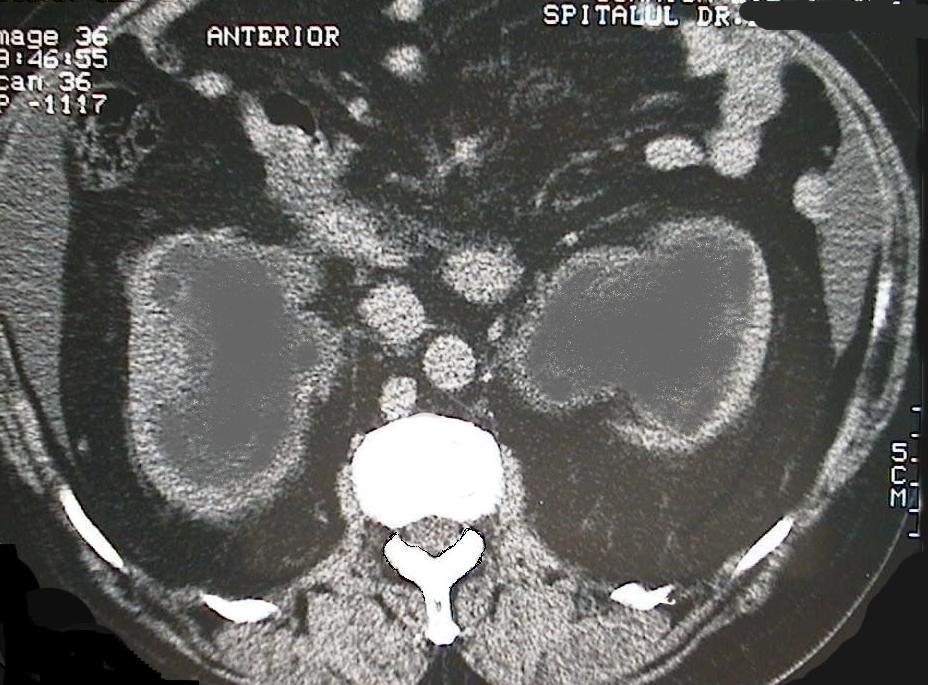

Computerized Tomography (III): masive bilateral hydronephrosis which compresses renal cortex.

Tomografie computerizată (III): hidronefroză masivă bilaterală cu compresiunea corticalei renale.